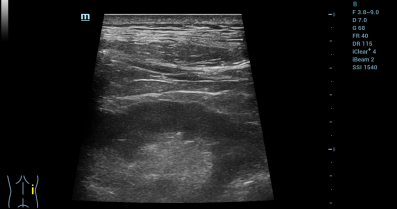

细胞移植环节采用「肾脏专科+超声影像专科」联合诊疗模式,实施超声实时引导下精准肾内靶向注射。操作者在术前对患者进行细致的双肾影像学评估,在超声实时观察下精准测算肾脏皮质厚度、肾动脉内径及解剖走向,规划最优进针角度与安全路径。术中采用局部微创麻醉,在超声定位给药点进针,实时引导患者呼吸节律调控,规避脏器牵拉风险。在超声仪探头实时检测的同时,经皮精准穿刺至肾实质中带定位给药,靶向富集于肾损伤区域。

细胞移植完成后结合CDFI彩色血流成像复核,确认给药位点精准、无活动性出血及肾周渗漏。患者术中全程清醒耐受良好,无即时不良反应。细胞移植后0天至3天短期随访数据显示,患者生命体征平稳、自主活动正常,无感染、发热及注射并发症。细胞移植后3天患者总蛋白、白蛋白指标由术前长期低于正常值水平(分别为60.4 g/L和37.8 g/L)提升至正常水平(65.2 g/L和40.9 g/L),短期内初步验证了给药安全性与修复疗效。

术后超声复查,示肾周及集合系统结构清晰,未见异常征象。